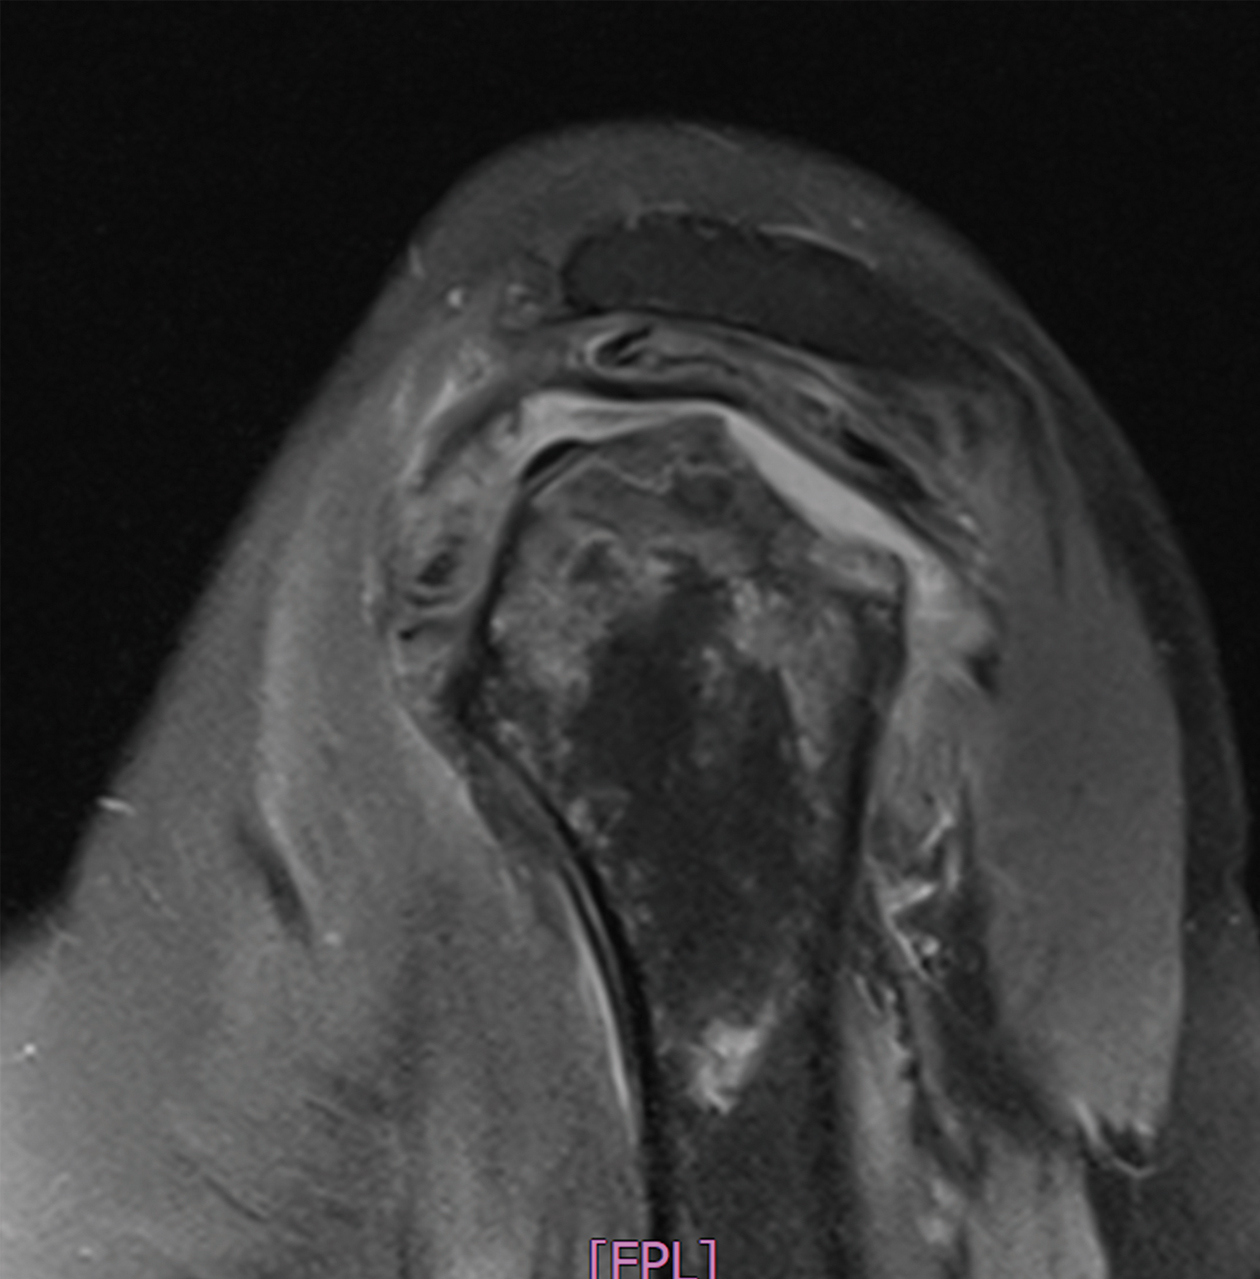

黃先生52歲,左肩疼痛多年,手無法上舉,一年來症狀加劇,經檢查發現肱骨頭缺血性壞死併肩關節炎,核磁共振發現大片全層旋轉肌破裂,接受了反置式人工全肩關節置換手術治療,並投入計劃性復健治療,目前疼痛消失,手已可上舉接近150度。

左側肱骨頭缺血性壞死續發關節炎併旋轉肌腱斷裂,經反置式人工全肩關節置換手術治療。